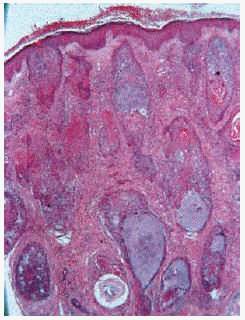

Las formas de mucinosis folicular primaria localizada y de mucinosis folicular primaria difusa fueron similares histológicamente. Se caracterizaron por abundantes depósitos de mucina en el folículo y una intensa destrucción folicular (figs. 6 y 7), que en ocasiones se acompañaba de granulomas foliculares secundarios. El infiltrado inflamatorio era escaso, de distribución superficial y perifolicular, sin atipias ni epidermotropismo. Los eosinófilos fueron escasos o ausentes en el infiltrado.

Fig. 6.--Mucinosis folicular localizada a pequeño aumento.